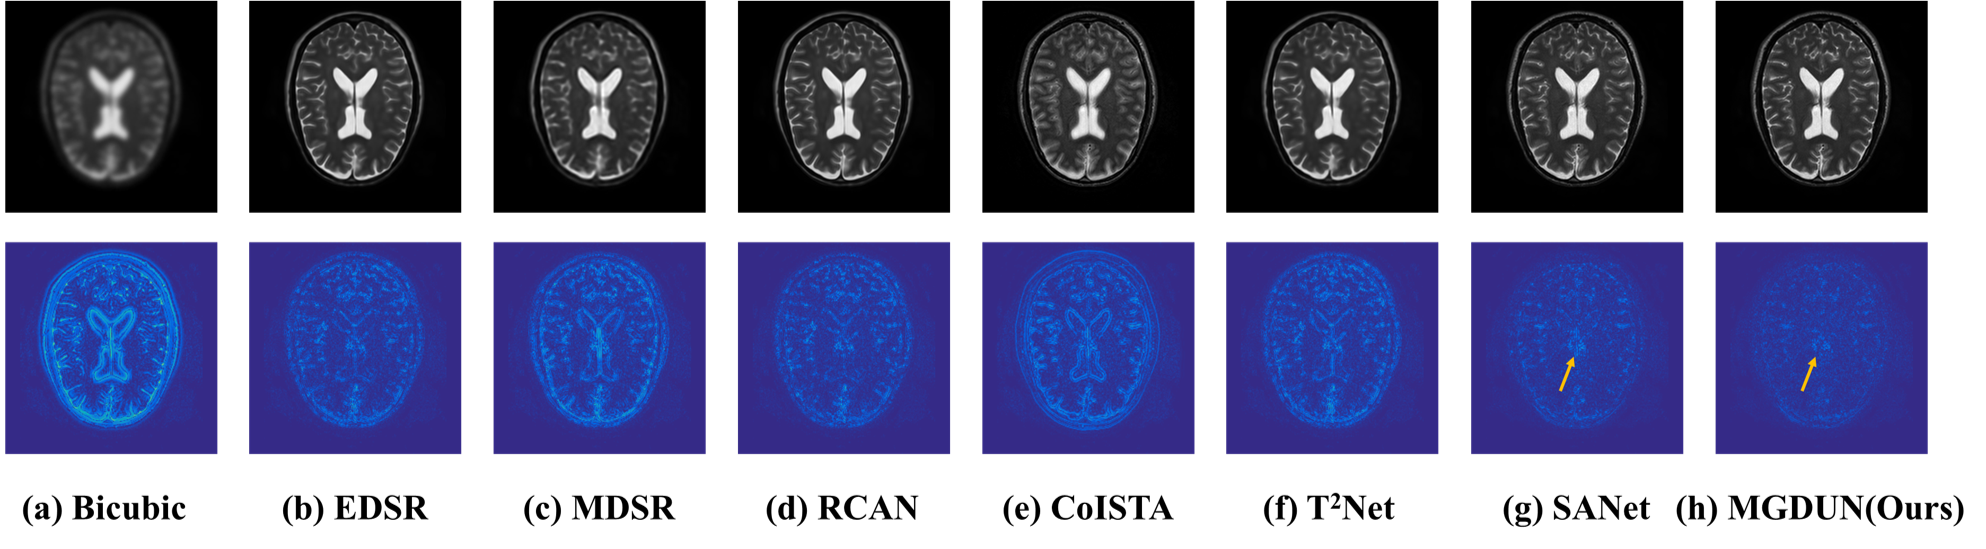

4.3.2. Qualitative results

We provide qualitative comparison results on the IXI dataset as well as the BraTs dataset and their corresponding error maps in Fig. 3 and Fig. 4. The texture of error maps represents the restoration error, the smoother the texture, the better the reconstruction. As we can see, the input has significant aliasing artifacts and lacks anatomical details. It can be noted that our model recovers the image with fewer visible artifacts and reconstructs more details than other competing methods. The quality improvement achieved by MDCUN may be associated with the full usage of the feature maps from the former stages to refine the final results.